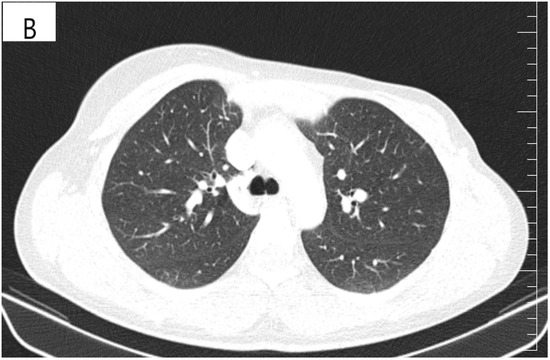

Figure 4.

(A) Pretreatment CT scan of the lungs showing interlobular septal thickening and multiple bilateral peribronchovascular nodular opacities. (B) CT scan showing resolution of interlobular septal thickening and remission of most of the pulmonary nodules after treatment with six cycles of Pertuzumab, Trastuzumab and Paclitaxel.